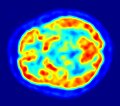

PET-Hirnaufnahme (axiales Schnittbild) -